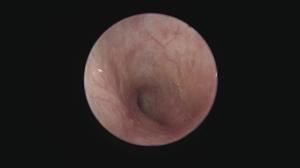

鼓膜付近の耳垢塊です。通常の洗浄や点耳薬では除去できないため、外耳炎が治りにくい状況になります。

このような場合、耳内視鏡による摘出と鼓膜付近の丁寧な汚れの除去が必要です。